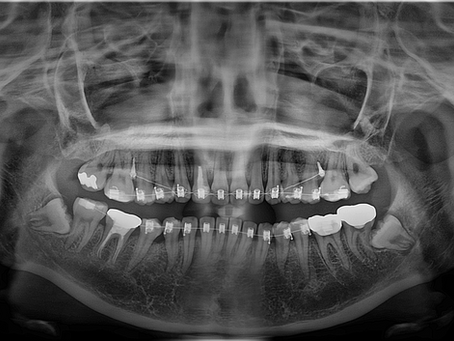

부산교정 + 충치 + 사랑니 발치 통합치료가 가능한 키다리아저씨치과 치료사례